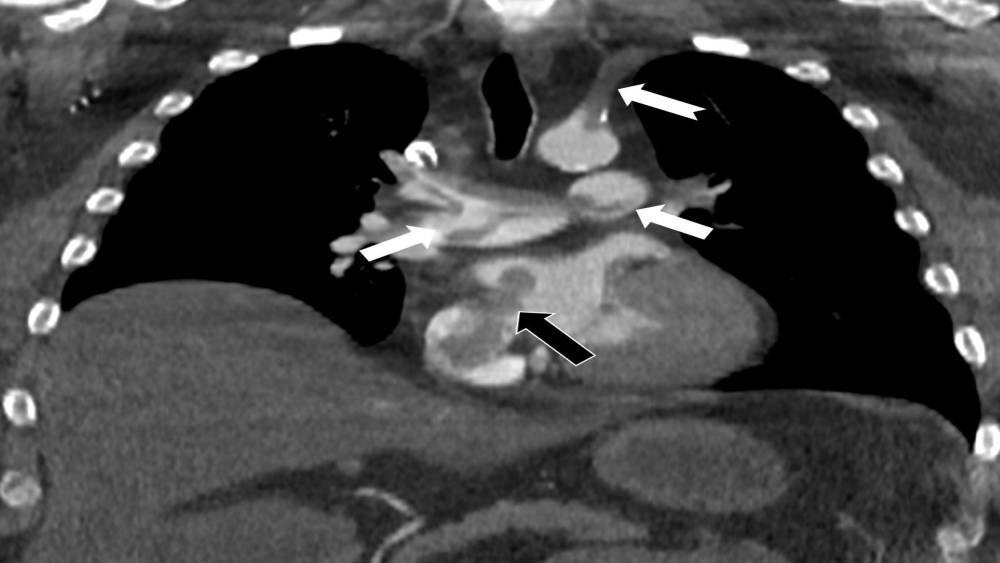

Kalp ve akciğer görüntülemesi alanındaki uluslararası bilimsel çalışmalarıyla tanınan Radyoloji Uzmanı Prof. Dr. Nevzat Karabulut, dünyanın önde gelen tıp dergilerinden Radiology dergisinin 2025 Kasım sayısında yayımlanan "Paradoxical Embolism with Clot-in-Transit in Atrial Septal Defect" adlı çalışmasında, penis ameliyatından 5 gün sonra ani göğüs ağrısı, nefes darlığı ve kol uyuşması şikâyetiyle hastaneye başvuran 60 yaşındaki bir hastada, daha önce fark edilmemiş kalp odacıkları arasındaki bir delikten geçen pıhtının hayati tehlike oluşturduğunu ortaya koydu.

Bir dönem Özel Denizli Tekden Hastanesi’nde de görev yapan Prof. Dr. Nevzat Karabulut’un yaptığı çalışmada; akciğerin bilgisayarlı tomografi anjiyografisi sayesinde toplar damarlardan kaynaklanan pıhtının akciğer damarlarını tıkaması yanında, kalpteki delik nedeniyle kalbin sağ tarafından sol tarafına geçerek ana atardamara ulaştığı ve sol kol damarını tıkadığı gösterildi.

Emboli görüntülemesi konusunda çok sayıda bilimsel çalışması bulunan Prof. Dr. Karabulut, genelde bacak damarlarından kaynaklanan pıhtıların ölümcül olabilen akciğer embolisine yol açması yanında, kalp deliği olan hastalarda ana atardamar yoluyla beyin, kol ve bacak gibi vücudun diğer bölgelerine de geçerek ani damar tıkanmasına (paradoks emboli) bağlı bulgulara yol açtığını belirtti. Prof. Dr. Karabulut’un çalışmasında nedeni bilinmeyen pıhtı atmalarında kalpteki gizli deliklerin mutlaka araştırılması gerektiği vurgulanarak ekokardiyografi ve bilgisayarlı tomografi tetkiklerinin erken ve doğru tanı koymada hayat kurtarıcı rolüne dikkat çekildi.